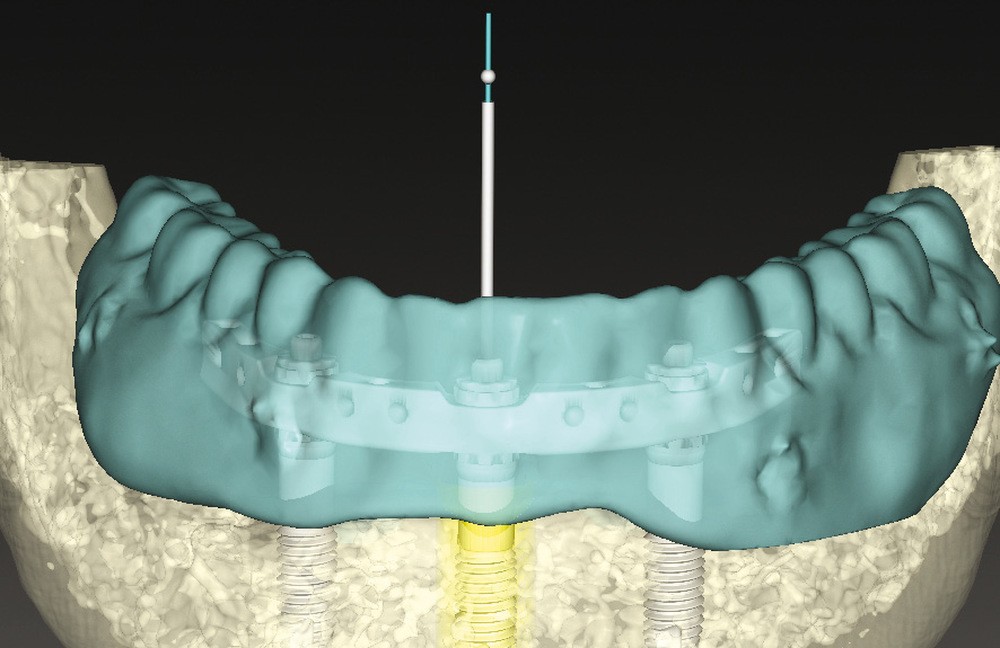

La planification virtuelle implantaire s’ensuit. Une fois encore, le numérique conforte ses atouts. Les matchings, sous réserve d’une parfaite correspondance, offrent une multitude d’informations optimisant la parfaite concordance entre anatomie osseuse, implants (3 CC RP 5×11,5mm), barre Trefoil et montage directeur (fig. 3). Cette somme d’informations permet alors de visualiser la barre Trefoil au travers du montage directeur.

La prothèse mandibulaire virtuelle recouvre parfaitement la barre digitale et les puits de vissage se trouvent en lingual des dents prothétiques. Cette prothèse pourra donc être conservée en tant que bridge d’usage, ce dernier étant dupliqué en guide radio-chirurgical implantaire de première intention. Turbine, contre-angle et cheville sont connectés en haut débit !

La prothèse mandibulaire, futur bridge d’usage [6], est évidée en lingual afin de visualiser et contrôler le positionnement de la barre. Temporairement, le volet vestibulaire et les trigones sont conservés, ainsi que les 7, pour assurer une sustentation et occlusion optimales lors de la solidarisation clinique.